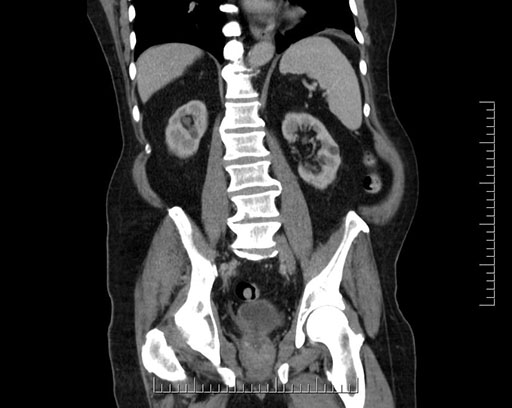

Imaging Analysis

Look through the patient's CT scan to identify any areas of concern for the necessary procedure.

Based on your CT findings, which issue(s) would give reason for "planned slowing down moment(s)" in this case?